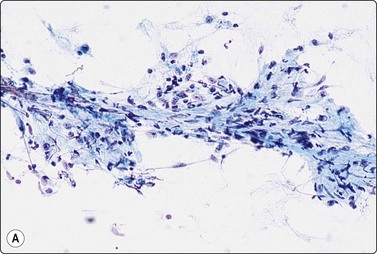

image image

Fig. 7.1 Radiation-induced atypia

(A) The epithelial cells in this irregular cluster show considerable nuclear enlargement, pleomorphism and hyperchromasia, but also some degenerative changes such as loss of nuclear structure (MGG, HP); (B) Corresponding tissue section (H&E, IP).